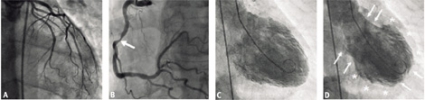

EKG i akutskedet påvisade sinustakykardi med utbredda ST-segmentförhöjningar över bröstavledningarna V1–V6 (Figur 1 A). Akut koronarangiografi visade normal vänster koronarartär och 55 procents stenos i höger kranskärl enligt datorbaserad tolkning (Figur 2 A och B). Kontrastinjektion i vänster kammare visade akinesi i mellersta delen både anteriort och inferiort med hyperkinesi i de apikala och basala delarna, vilket gav vänsterkammaren ett karakteristiskt, ballongliknande utseende under systole (Figur 2 C och D). Denna karakteristiska ballonering av vänster kammare kunde också påvisas vid ekokardiografisk undersökning. Hjärtskademarkören troponin I var måttligt förhöjd (7,1 µg/l), varför takotsubosyndrom misstänktes.